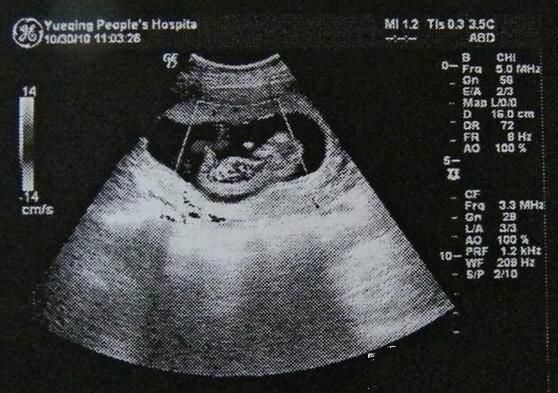

而在医学临床上应用的超声诊断也不只B型超声一种,还有A型、M型、D型等。不过B超的确是临床上应用最广泛便捷的那一个。B超通过平面图形来显示被探查组织的具体情况。这是一种亮度调制型的黑白灰图像,展现的是组织器官的二维切面图。白色、灰色、黑色的灰度变化显示脏器或组织的物理特性变化,从而反映组织的结构和病变情况。比如遇到回声强的组织器官,返回波的光点图像就亮,呈现白色,如胆结石、胎儿的脊柱等;而在体内液体中的传播,因为没有回声,则呈现黑色,如腹腔的出血、孕妇的羊水等。B超在反映人体内脏器官的切面图形方面清晰直观,因此常被用于肝、胆、胰、脾、肾、子宫等脏器疾病的诊断。但B超也有它的弱点,容易受到肠气的干扰,因为超声波波长很短,在空气中极易损耗,容易散射,遇到气体会影响成像。